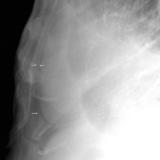

Case 3 Lat only

Peric calcification

Date: 03/17/2004

Views: 8419